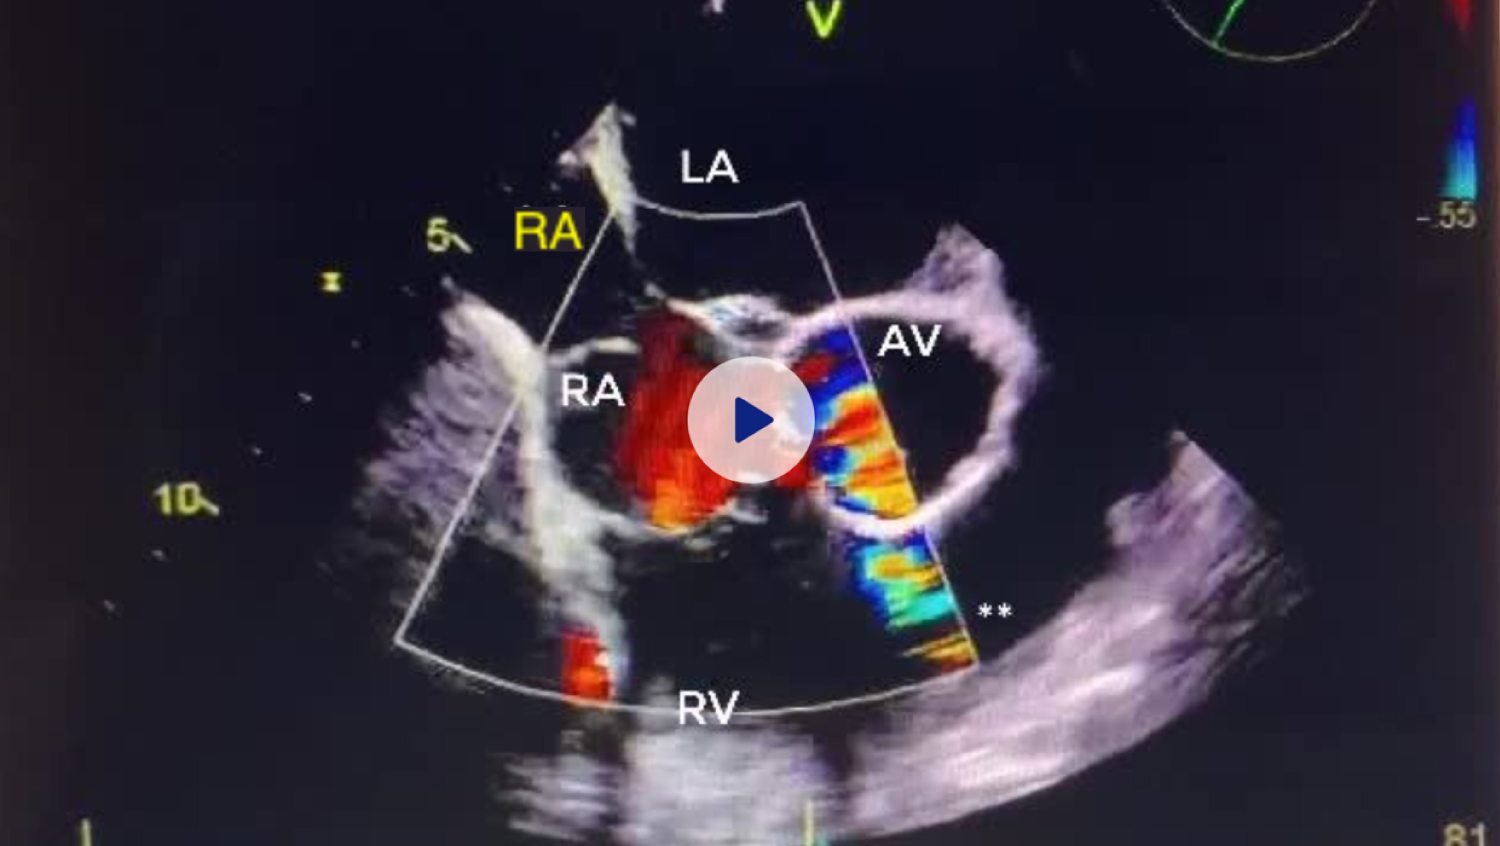

Figure 2: Transesophageal Echocardiogram with color flow doppler demonstrating Cor Triatriatum Dexter with blood flow into the right ventricle.

RA: Right Atrium; RV: Right Ventricle; LA: Left Atrium; LV: Left Ventricle View Figure 2

Figure 3: Transesophageal Echocardiogram with color flow doppler demonstrating Cor Triatriatum Dexter with blood flow between right atria. A small patent foramen ovale is also visible between right and left atria.

RA: Right Atrium; RV: Right Ventricle; LA: Left Atrium; LV: Left Ventricle View Figure 3